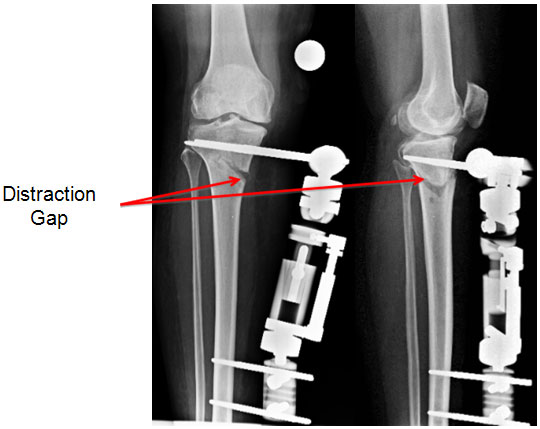

HTO done with external fixator LRS